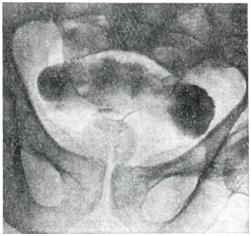

Применяют экскреторную урографию, цистографию и уретроцистографию; наиболее рациональна лакунарная уретроцистограмма по Кнайзе и Шоберу (рис. 4). Кислород, введенный по катетеру в количестве 150—200 мл, растягивает мочевой пузырь в виде купола. Введенное вслед за кислородом жидкое контрастное вещество (20% раствор сергозина в количестве 20 мл) располагается в области дна мочевого пузыря, выявляя внутрипузырный рост аденомы предстательной железы. Этим методом определяют ряд типичных рентгенологических симптомов: «берета» (рис. 5), удлинения мочеиспускательного канала (рис. 6), «клинка сабли» (рис. 7), приподнятого дна.

Экскреторная урография, помимо определения функции почек, указывает на состояние нижних отрезков мочеточников, которые крючкообразно приподнимаются кверху, давая изображение «рыболовного крючка» (рис. 8). Рентгенологическое исследование выявляет также сопутствующие заболеванию камни и дивертикулы.